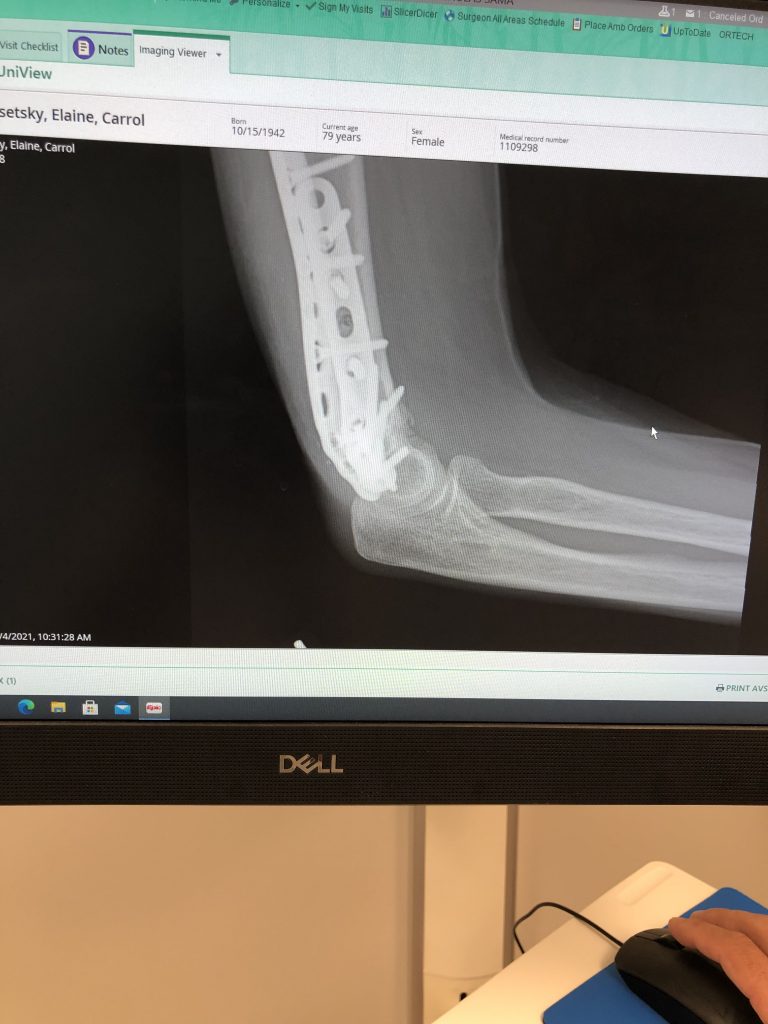

Dr. Sama is a skilled surgeon that is a master in repair. He used plastic surgery stitches upon closing the wound. This picture is 11 weeks into healing and you can barely notice. I have returned to 100% functioning to the surprise of PT and myself. I am so grateful to this wonderful surgeon who is also compassionate and generally a really nice guy. Thank you.